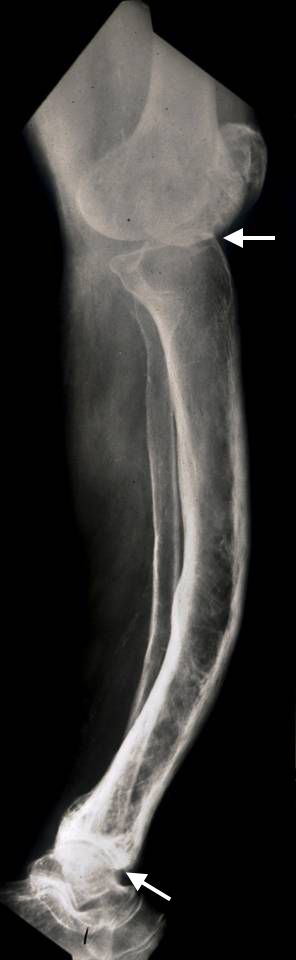

Paget's disease of the tibia

X-ray shows bowing of the tibia (shinbone) in a patient with advanced Paget's disease. Arthritic changes, including joint space narrowing, are also present in the knee and ankle joints (arrows).

Reproduced from Moon BS, Luna JT, Raymond KA, Madewell JE: Paget’s disease of bone. Orthopaedic Knowledge Online Journal 2010; 8(1). Accessed June 2017.